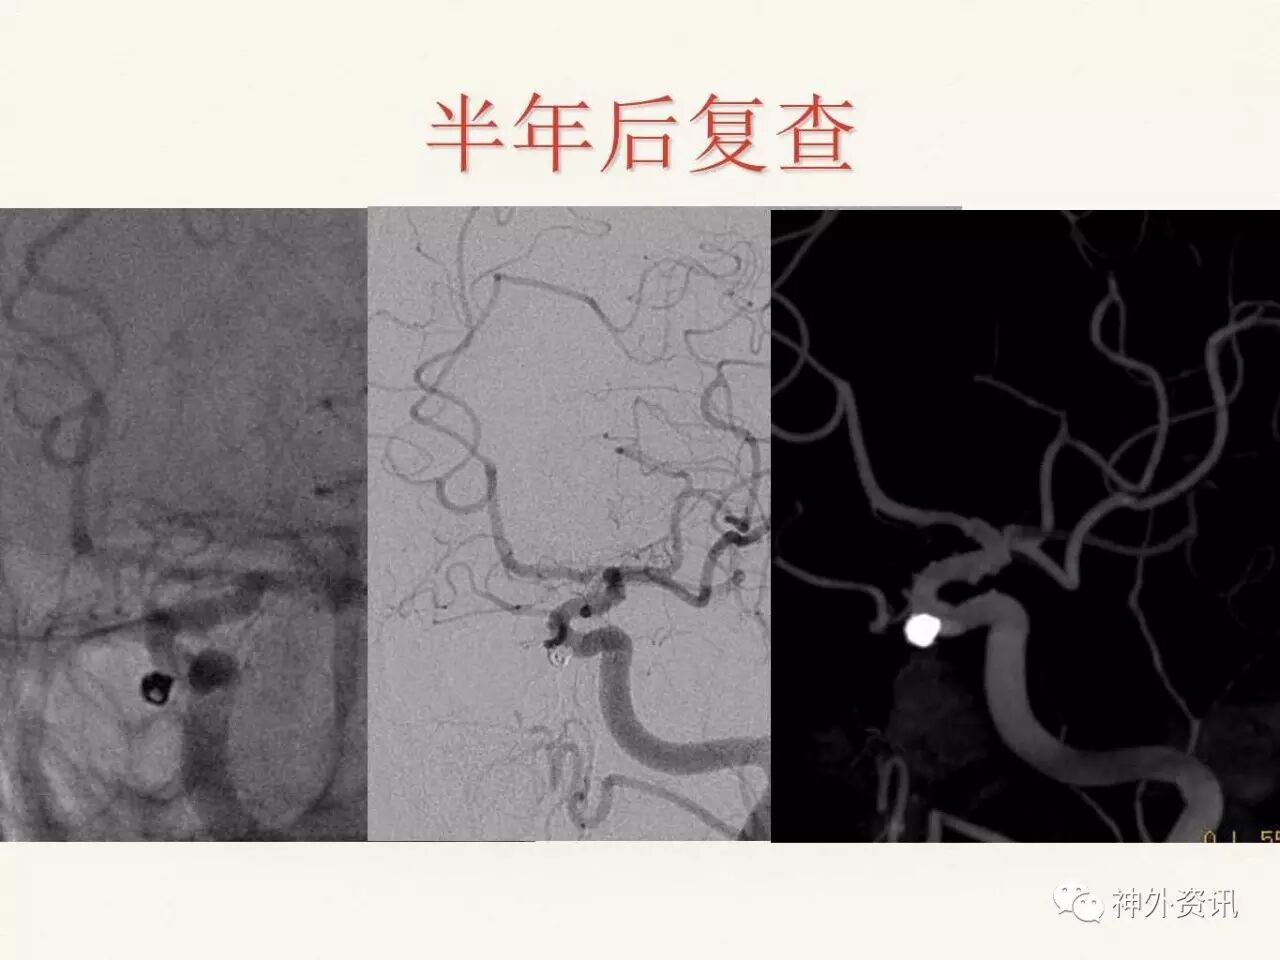

在东北地区率先开展了颈内动脉、大脑中动脉及基底动脉闭塞血管内再通、颅内动脉栓塞急性期取栓、血流导向装置治疗大型宽颈动脉瘤等,对颅内动脉瘤、动静脉畸形、颈动脉及颅内动脉狭窄、颈内动脉海绵窦瘘、硬脑膜动静脉瘘等外科治疗具有较深的造诣。完成脑血管造影8600余例,各类脑血管病介入手术共4500余例,动脉瘤、动静脉畸形、脑肿瘤、脑出血及脑外伤等外科手术1500余例。